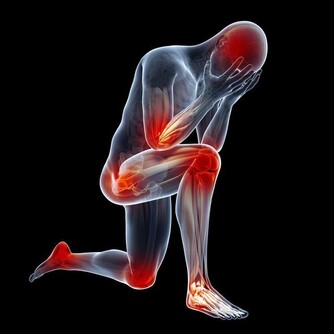

肝癌的發生並不是悄無聲息的,在肝癌發生初期,是有一定的症狀存在可以起到疾病的提示作用的。下面專家就肝癌的早期症狀做了介紹。 出血傾向:癌患者常有牙齦出血、皮下淤斑等出血傾向,主要是由於肝功能受損、凝血功能異常所致,它在肝癌合併肝硬化的患者中尤為多見。消化道出血 較為常見,主要是由於門靜脈高壓導致食管胃底 靜脈曲張 所致。事實上,消化道出血也是導致肝癌患者死亡的最主要原因。 下肢水腫:肝癌伴腹水的患者,常有下肢水腫,輕者發生在踝部,嚴重者可蔓延至整個下肢。臨床上曾見到有的患者下肢高度水腫,水液能從大腿皮膚滲出。造成下肢水腫的主要原因是腹水壓迫下肢靜脈或癌栓阻塞,使靜脈回流受阻。輕度水腫亦可因血漿白蛋白過低所致。 文章導讀

消瘦乏力:肝癌患者常較其他腫瘤患者更感乏力,此與慢性 肝炎患者相似。乏力的原因不明,可能由於消化功能紊亂、營養吸收障礙導致能量不足,或肝細胞受損,肝功能下降,使得代謝障礙、某些毒素不能及時滅活,或由於肝癌組織壞死釋放有毒物質。消瘦也是肝癌患者的常見症狀,系由於肝功能受損。消化吸收功能下降所致。隨著病情的發展,消瘦程度可加重,嚴重時出現惡病質。 發熱:相當一部分的肝癌患者會出現出汗、發熱。多數發熱為中低度發熱,少數患者可為高熱,在39℃以上,一般不伴有寒戰。肝癌的發熱多為癌性熱,這是因為腫瘤組織壞死後釋放致熱原進人血液循環所致。腫瘤患者由於抵抗力低下,很容易合併感染,亦可出現發熱,與肝癌的癌性發熱有時不易區別,需結合血象並觀察抗菌治療是否有效才能判定。 消化道症狀:食慾下降、飯後上腹飽脹。曖氣、消化不良、噁心等是肝癌常見的消化道症狀,其中以食慾減退和腹脹最為常見。腹瀉也是肝癌較為常見的消化道症狀,國內外均有報道,發生率較高,易被誤認為慢性腸炎。門靜脈或肝靜脈癌栓所致的門靜脈高壓及腸功能紊亂可致腹脹、大便次數增多,腹脹亦可因腹水所致。胃腸功能紊亂還可導致消化不良、曖氣、噁心等症狀。 來源: 大眾養生網